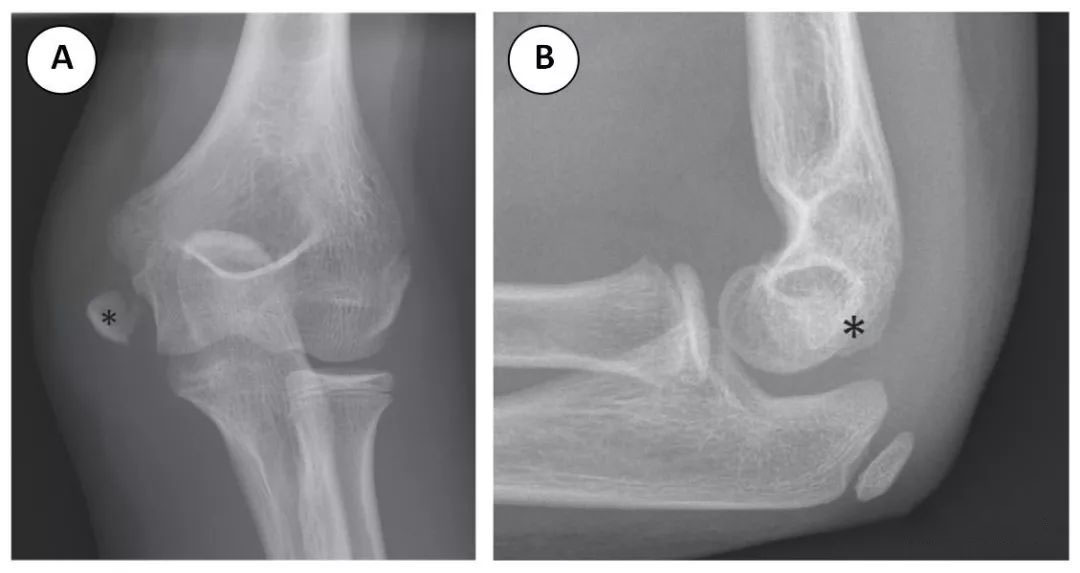

肱骨内髁骨折在儿童肘关节骨折中占第三位,约 10%。10 肱骨内上髁是一隆起,是屈肌腱的共同附着部位。内上髁骨折发生在青少年早期,相对于髁上、外髁骨折人群,内上髁骨折发生的年龄偏大。患者摔倒后伸肘,导致肘部急性外翻应力。外翻应力引起内上髁撕脱性骨折,由屈肌腱和旋前肌腱共同作用导致 (图 7)。13 由于内上髁是一个关节外骨结构,肱骨内上髁骨折往往不会导致关节积液 (图 7B)。其中,30%-50% 的内上髁骨折与肘关节脱位有关。14 当肘关节脱位时,内上髁撕脱,有时夹在肱尺关节内 (图 8A)。放射科医师必须认识这种复杂的骨折,以避免延误诊断和防止肘关节破坏。CT 可用于确定向肱尺关节内移位的内上髁,特别是在未完全骨化和 (通常) 碎片化的滑车骨化中心的潜在混乱环境中 (图 8B 和 C)。肱骨内上髁骨折的处理取决于移位的程度。如无移位或移位小于 5mm,则石膏制动治疗。如骨折块移位大于 5mm 或夹在肘关节内,则最好采用切开复位穿针内固定。14,15

图 7 9 岁女子体操运动员从平衡木上摔下后肘部内侧疼痛。(A) 肘关节正位片示内上髁撕脱性骨折 (星号),骨折向远端移位。(B) 肘部侧位片图。注意,无关节积液。此外,内上髁 (星号) 位于肘关节的背侧。随着进一步的撕脱,内上髁将进一步移动到肘关节的前 / 掌侧。